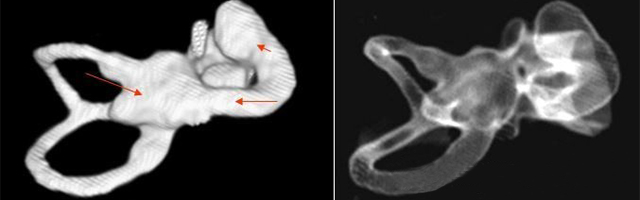

主要根據(jù)聽力學表現(xiàn)和影像學檢查。通過高分辨CT可看到耳蝸畸形。內耳MRI顯示膜迷路內水充盈,耳蝸扁平,耳蝸第二圈與頂圈間隔缺損,以及半規(guī)管、前庭的畸形。

先天性耳蝸畸形伴前庭和外半規(guī)管發(fā)育不良

主要依靠顳骨高分辨CT和內耳MRI。

雙側內耳畸形:左側無內耳迷路及內耳道機構,為米歇爾畸形;右側空耳蝸及前庭擴大,為先天性耳蝸畸形